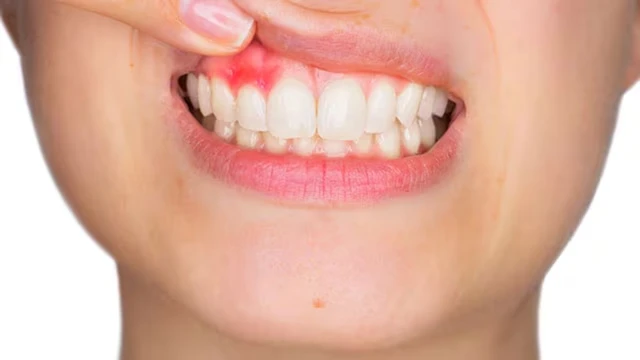

/https://cms-prod.s3-sgn09.fptcloud.com/nuou_rang_bi_do_1_2f1a3f9dd4.jpg)

Nướu răng bị đỏ cảnh báo điều gì? Cần chăm sóc răng miệng và điều trị như thế nào khi bị đỏ ở nướu răng? Bài viết dưới đây sẽ giúp bạn hiểu rõ về nguyên nhân và cách khắc phục tình trạng nướu răng bị đỏ.